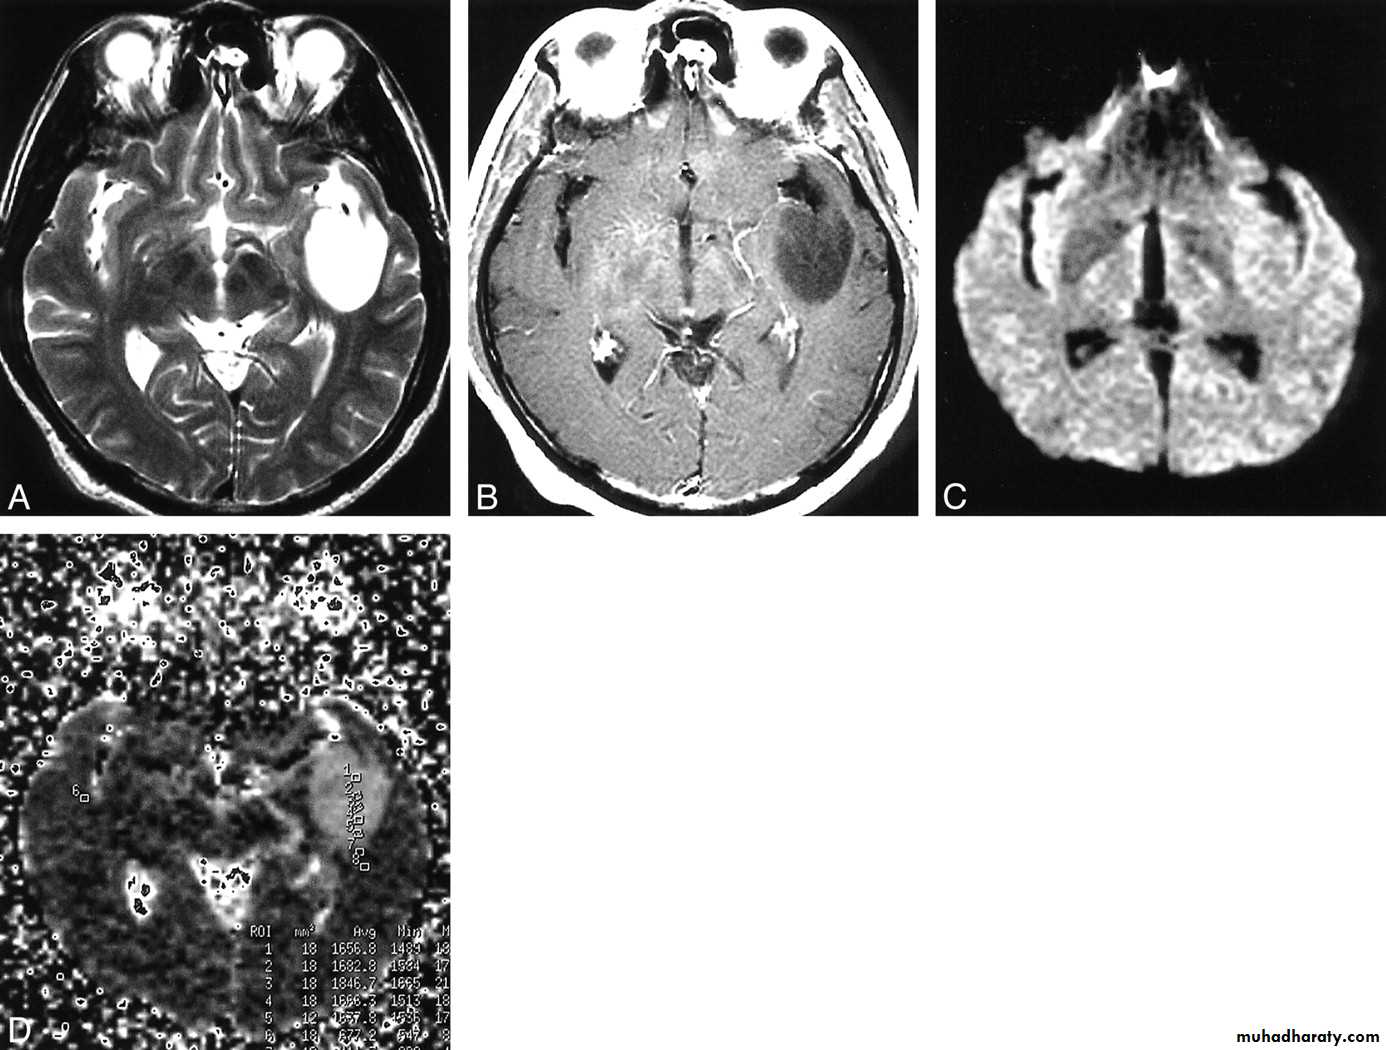

GLIOBLASTOMA MULTIFORMI

GM AXIAL MRI